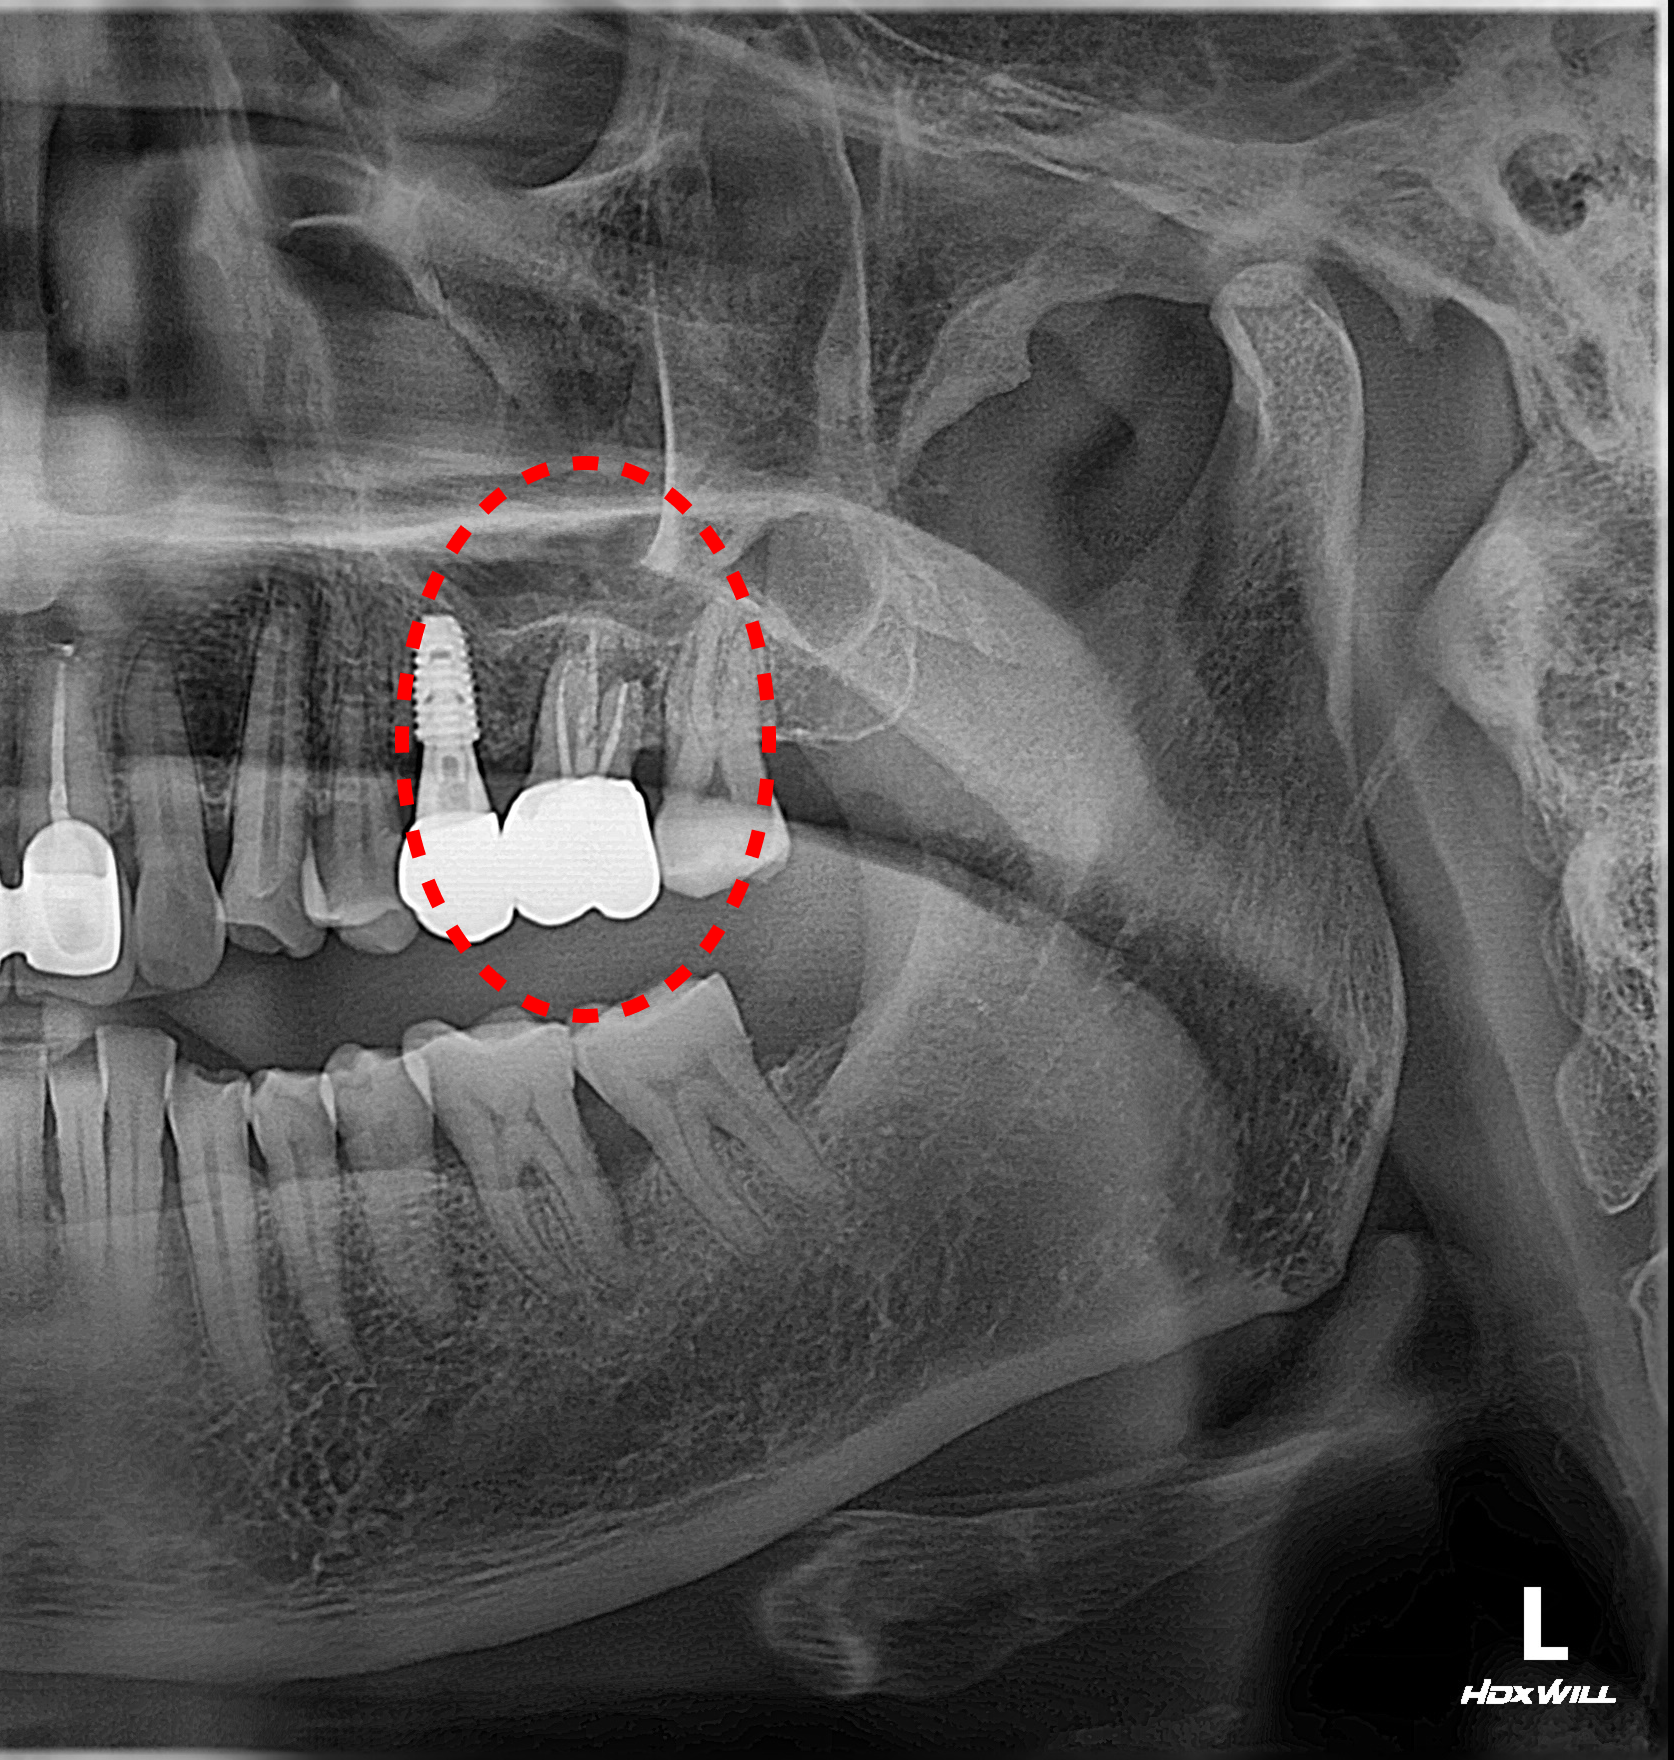

5개월의 치유 기간을 거친 후, 임플란트 식립 수술을 진행했습니다.

하지만 상악(위턱) 어금니 부위는 해부학적으로 '상악동'이라는 공기 주머니 형태의 빈 공간이 존재하여 본래 잔존골의 두께가 얇은 편입니다. 이에 더해 환자분은 이전의 심한 염증으로 인한 골흡수까지 겹쳐, 임플란트를 지지할 치조골이 절대적으로 부족한 상태였습니다.

안전한 식립 깊이를 확보하기 위해 상악동의 하연 막을 조심스럽게 위로 들어 올리고, 그 하방 공간에 골이식재를 채워 넣는 '상악동 거상술'을 시행했습니다. 수술 시 절개 횟수와 환자의 부담을 줄이기 위해, 거상술 시행과 동시에 임플란트 픽스처(인공 치근) 식립을 병행하여 마무리했습니다.